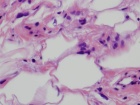

68 year old female with painless mass in right forearm

Zoom image: Cell stain Cell stain.